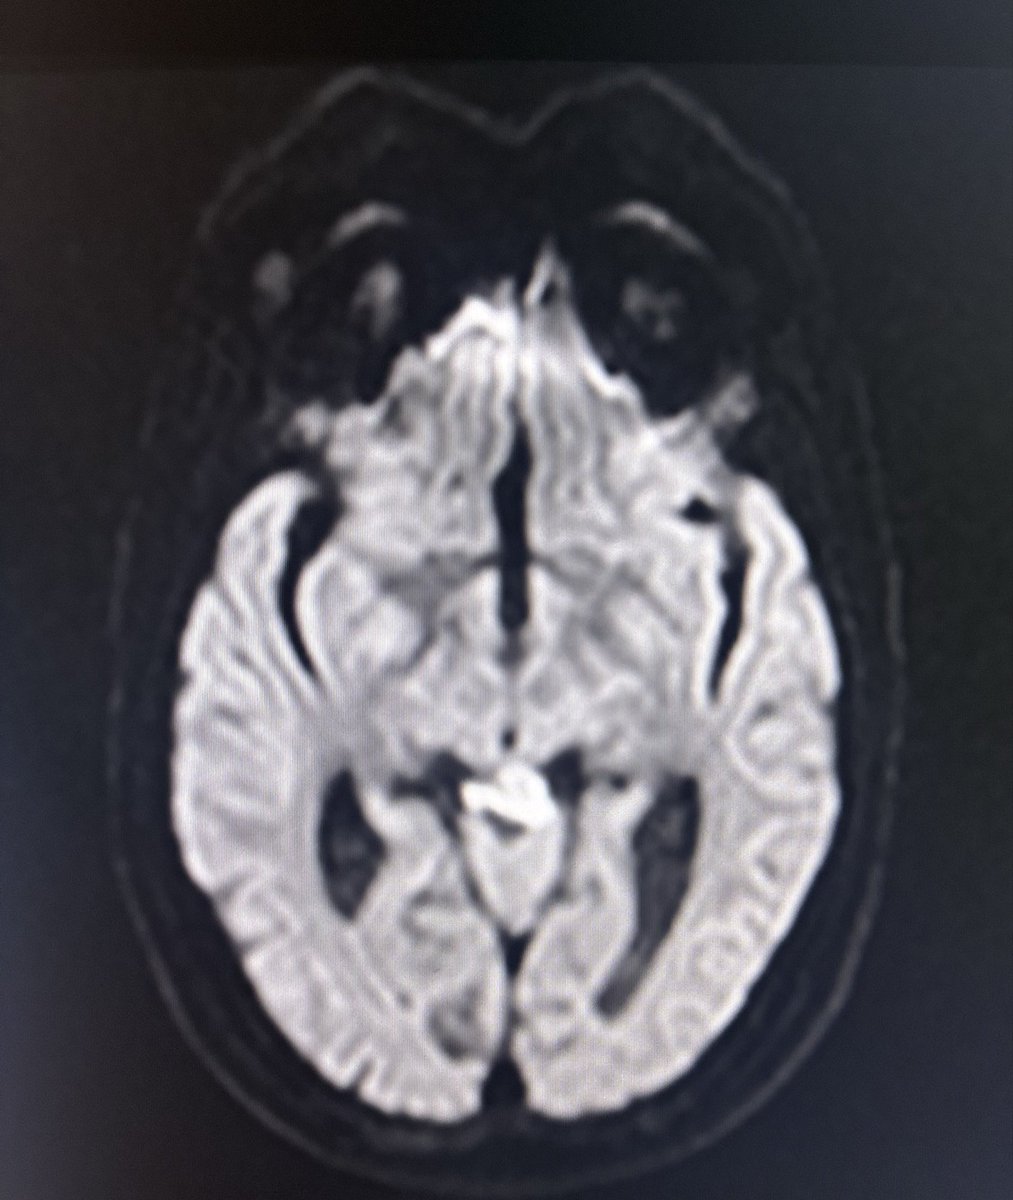

67 year old male with headache.

Contrast images are in 🧵.

#MedTwitter

#RadX #Radtwitter

#Neurorad

#NeuroTwitter

This case is a reminder that Age, Gender, location of lesion, They all point to help narrow the differential diagnosis apart from signal characteristics when we report images.

Lesion in left cerebellum - T2 hyperintense lesion, no diff restriction, intense enhancement with feeding vessels also seen on T2 as flow voids - posterior fossa tumour in elderly male - highly in favour of Hemangioblastoma - DD is metastasis.